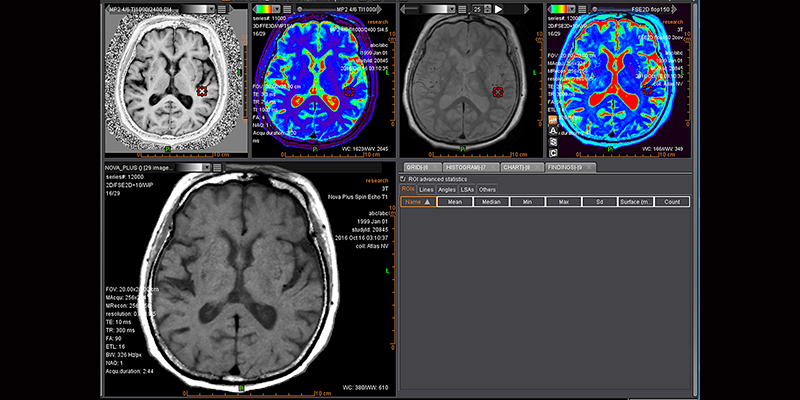

Клінічний додаток Olea Nova+ для МРТ​​​​​​​

Olea Nova+ - це вдосконалений плагін постобробки даних MРТ, який пропонує метод автоматичного обчислення рутинних зображень із спеціалізованого протоколу.

Клінічний пакет МРТ

Клінічний пакет МРТ, розроблений компанією Olea Medical включає аналіз дифузії, перфузії і оптимізовані до сучасних протоколів стандартні автоматизовані програмні пакети для різноманітних органів. Цей пакет допомагає покращити обробку даних та полегшити роботу з рутинними діями.

Додаток Аналіз візуалізує, сегментує, вимірює та оцінює широкий спектр наборів даних від звичайних серій до перфузійних та кінетичних серій разом із серіями DTI та DWI. Він забезпечує визначені користувачем накладання, включаючи візуалізацію органу/або патології, аналіз кінетики та кривих, аналіз кривих, статистику, співвідношення та гістограми, синтез декількох серій, напівавтоматичне сегментування об’єму, рендеринг об’єму та подальші динамічні спостереження.